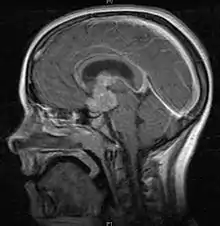

یک تصویر ساژیتال از مغز. قدرت تفکیک پایین تصویر بدلیل آرتیفکت حرکتی است.

این آرتیفکت غالبا با کاهش قدرت تفکیک و در جهت کد گذاری فازی (PE) در تصویر قابل رویت است.